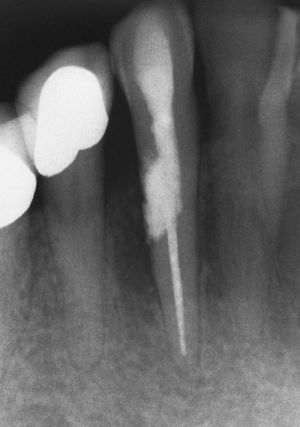

SintomatologíaLos dientes afectados pueden permanecer asintomáticos durante mucho tiempo. La prueba de sensibilidad puede ser positiva o negativa en función de la localización. Las profundidades de sondaje no están alteradas y no se observa movilidad dentaria. El diagnóstico suele ser el resultado de un hallazgo radiográfico casual (figs. 3 y 4) o producirse a raíz de una perforación y de una infección secundaria por la expansión del proceso original. El proceso se puede transparentar en forma de mancha rojiza («pink spot») si la laguna de reabsorción se localiza en la zona de la corona.

Las reabsorciones internas se caracterizan por los signos radiográficos siguientes:

Ensanchamiento oval de la luz del conducto.

Lesión bien delimitada.

Lesión simétrica.

Posición estacionaria incluso en una proyección radiológica excéntrica complementaria.

Espacio periodontal continuo.